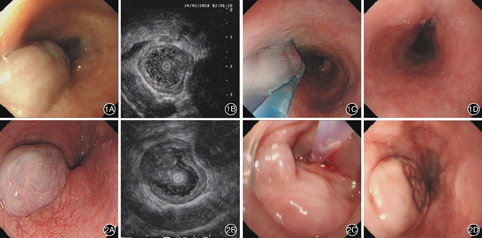

例1 患者女,73岁,因反复上腹胀伴胸骨后不适1个月余入院。胃镜下食管距门齿约20 cm处见一大小约10 mm×20 mm×15 mm的蓝色黏膜下隆起,表面光滑(图1A)。内镜超声:食管隆起处见一中低回声团块,切面大小约10 mm×15 mm,内部见分隔,多普勒见少许血流回声,边界清晰,向腔内突出,病变起源于黏膜下层,考虑食管血管瘤(图1B)。胸部CT示主动脉钙化。予内镜下硬化剂注射治疗。术前完善常规检查并签署相关知情同意书。丙泊酚麻醉下进行内镜操作,用25 G内镜注射针刺入瘤体见有血液回流,一次性注射含亚甲蓝的聚桂醇10 mL,见瘤体饱满、色泽发蓝即停止注射(图1C),复查内镜超声见病变回声明显增强后结束治疗。手术用时10 min。术后予吸氧、心电监护、禁食6 h,静脉使用质子泵抑制剂及抗生素。2周后患者胸骨后不适缓解,术后1个月复查胃镜见病变处食管表面光滑,未见瘤体残存(图1D)。

例3 患者男,63岁,因反复胸骨后疼痛不适3年,再发加重半个月入院。胃镜示食管距门齿约22 cm处一大小约12 mm×18 mm×26 mm的蓝色黏膜下隆起,表面光滑(图2A)。内镜超声:食管隆起处见一中低回声团块,切面大小约12 mm×18 mm,内部见散在点状强回声,多普勒见少许血流回声,边界清晰,向腔内突出,病变起源于黏膜下层,考虑食管血管瘤(图2B)。胸部CT平扫+增强+三维重建:食管胸上段低回声占位性病变,内见钙化灶。术前完善常规检查并签署相关知情同意书。25 G内镜注射针多次刺入瘤体后均未见血液回流,在瘤体根部四周分6点注射聚桂醇(因未有回血,聚桂醇中未加入亚甲蓝),每点1~2 mL,共10 mL,治疗后瘤体局部发亮(图2C),手术用时15 min。5 d后患者复查胃镜见食管瘤体明显萎缩,表面溃疡形成,未见活动性出血及其他并发症(图2D)。1个月后返院再次复查胃镜见瘤体完全消失,局部见一大小约4 mm×6 mm凹陷,内镜超声示黏膜层局部部分缺失,未见瘤体残留。